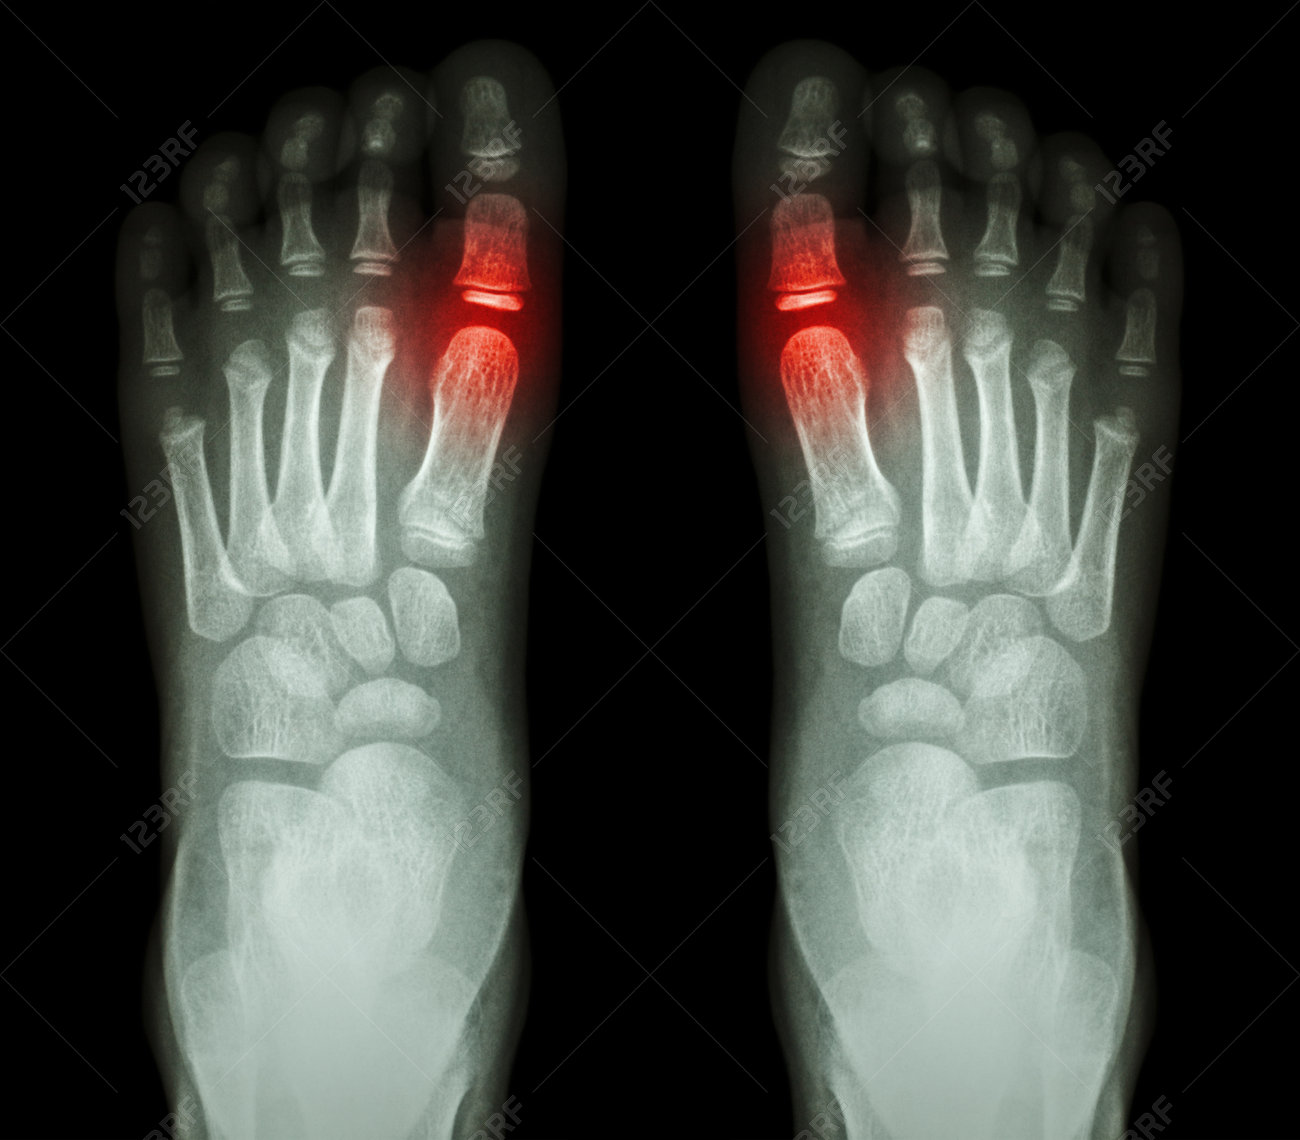

Rheumatoid Arthritis X Ray Stock Photo Alamy

Rheumatoid Arthritis X Ray Stock Photo Alamy from c8.alamy.com

The rheumatoid community on reddit. The earliest manifestation of rheumatoid arthritis of the forefoot is synovitis of the mtp joints with eventual hyperextension deformity of the mtp joints including distal. Rheumatoid arthritis (ra) imaging tests are used to look for signs of ra and to monitor the disease's progression. (uk) national rheumatoid arthritis society helpline. </b>small joints of the feet, wrists, and hands are frequently involved by a reduction of osteoporosis; Rheumatoid arthritis (ra) is a chronic autoimmune multisystemic inflammatory disease that affects many organs but predominantly attacks the synovial tissues and joints. Rheumatoid arthritis (ra) is the most common type of autoimmune arthritis. Rheumatoid arthritis is considered an indication for resurfacing of the patella during total knee arthroplasty.

If the pattern of disease is not symmetrical, then a different diagnosis should be considered. In rheumatoid arthritis, the body's immune system attacks its own healthy cells inside certain joints, leading to an inflammatory response. For more information and past images of the month, go to. However, they are not useful in the early stages of rheumatoid arthritis, before joint damage occurs. </b>rheumatoid arthritis (ra) is a polyarticular disease with bilateral and symmetric distribution. Sorptiometry should be performed to diagnose. The rheumatoid community on reddit. Rheumatoid arthritis (present for >10 years). The ulnar styloid is destroyed with the rest of the distal ulna (white arrow), there is destruction of the carpal bones (yellow arrow) and there is dislocation of the 1st metacarpal on the destroyed trapezium. Rheumatoid arthritis affects around 400,000 adults aged 16 and over in the uk. Reddit gives you the best of the internet in one place. Ra causes pain, swelling, stiffness, and loss of function in joints. The earliest manifestation of rheumatoid arthritis of the forefoot is synovitis of the mtp joints with eventual hyperextension deformity of the mtp joints including distal.